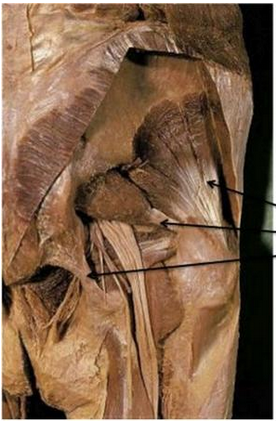

Name the structures attached to the 3 arrows

Top: Gluteus minimus

Middle: Piriformis

Bottom: Sacrotuberous ligament